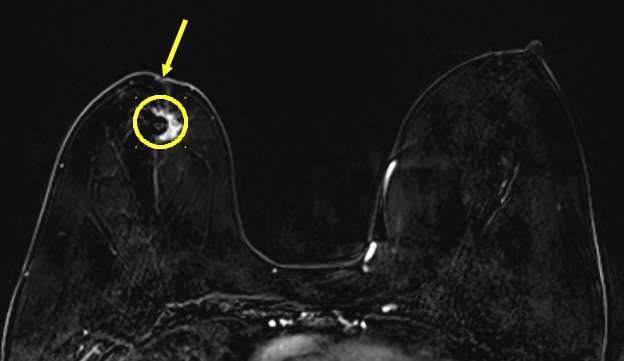

Case: Skin and Nipple Changes Figure 3

Figure 3: Nipple Retraction on mammogram. Patient presented for right nipple changes. Mammographic MLO and CC projections demonstrate a retracted nipple (arrows) overlying an irregular mass in the subareolar region with associated architectural distortion (circles) in the right breast. Left breast included for comparison.